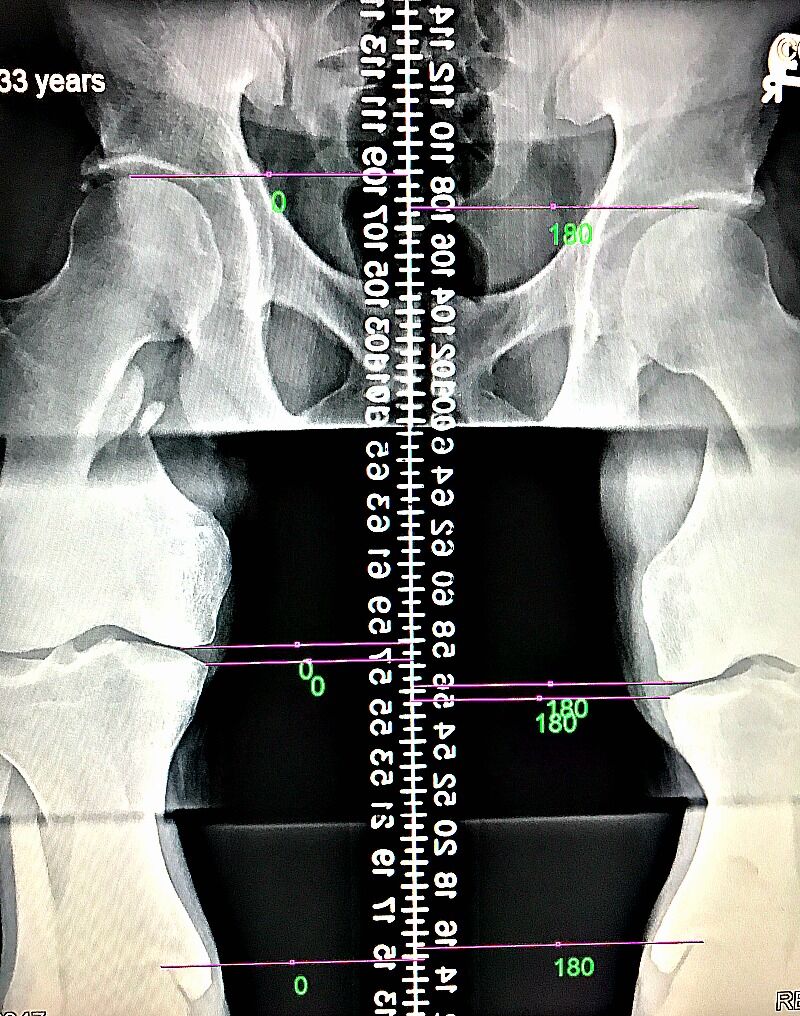

LLD may affect 60 – 90% of people, which is why it should be evaluated and considered a factor in patients seeking chiropractic care. Measurement by x-ray is the most accurate measurement method and since we’re looking at millimeters of difference, it is what we recommend.

After a physical examination, we will determine if x-rays are necessary. If we end up taking x-rays of the lumbar spine and pelvis, we will take measurements of the height of the femur heads to look for a measured difference. If a leg length difference greater than 3mm is present on x-ray, we will make note that the patient is a good candidate for a leg length discrepancy x-ray.

After several weeks of treatment, we will proceed with a leg length x-ray if warranted. Appropriate heel lifts or orthotics are recommended at that time. If the measured difference is greater than 5mm, the patient will start with a smaller heel lift and gradually increase to the closest possible difference.